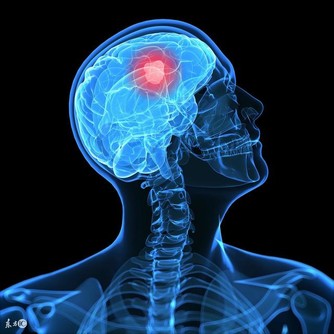

1、凌晨1-3點鐘莫名醒來,多由肝火旺盛所致。

常有煩躁、易怒或氣鬱等症狀,在氣血流注到肝經的時間段,自然把人喚醒。

2、一到凌晨3、4點就醒?也很可能是肝臟堵住了。

肝作為人體最為重要的代謝器官,如果肝不好的人,人的健康肯定是會受到影響的,而夜裡頻繁醒來,很可能就是肝出問題了。